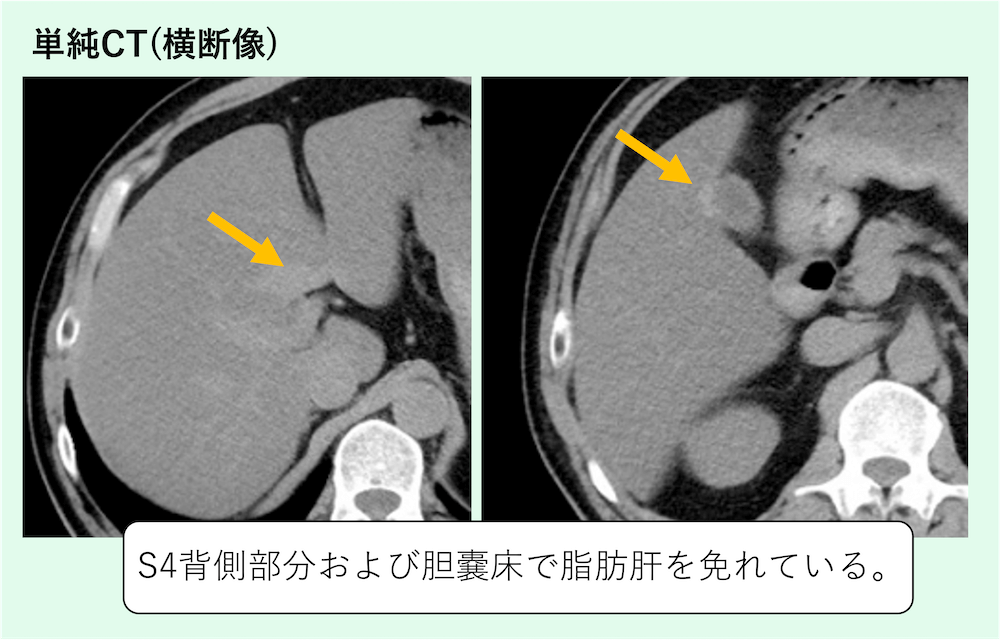

症例 70歳代男性

全体的に脂肪肝を認めますが、S4背側部分および胆嚢床で脂肪肝を免れていることがわかります。限局性非脂肪肝(focal spared area)を疑う所見です。